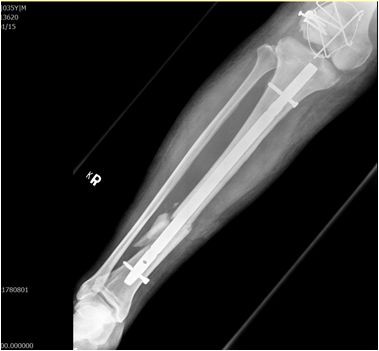

圖:手術治療前後的膝蓋與小腿。

而當時的主治醫師就是個性直率低調,被同事與後進同仁暱稱為鄺爺的骨科鄺世通醫師,這個在鄺醫師口中的小骨折,其實是包含髖關節、大腿股骨、膝蓋髕骨、與小腿脛骨等多處粉碎性骨折的複雜個案,不論是X光檢查,還是電腦斷層檢查,都能看見因為強力撞擊穿出髖關節的股骨,還有粉碎的髕骨,歷經數個小時的開刀,才救回洪國程先生的性命與右腿。

後來洪國程才知道,當時鄺醫師可以說是像是在拚一個摔破的瓷碗,一塊一塊地把他的骨頭拼回去,然後再細心的照顧他的傷口,才讓他免去截肢的痛苦,洪國程回想起來,心有餘悸的說:「當時我才35歲,正當年輕而且小孩還小,真的無法想像下半輩子要坐輪椅的生活。」